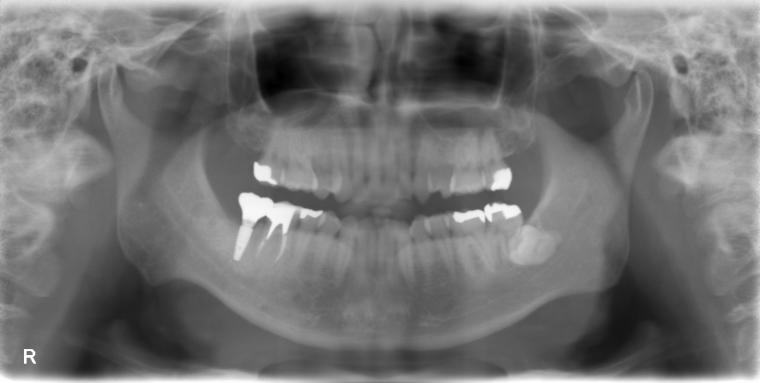

AFTER

38歳男性/下1本欠損/インプラント埋込手術

虫歯が進行していて、歯を保存出来なかったため歯を抜いて人工の骨を足してからインプラントを

1本埋込した患者さんです。

現在も定期検診で拝見させていただいてます。